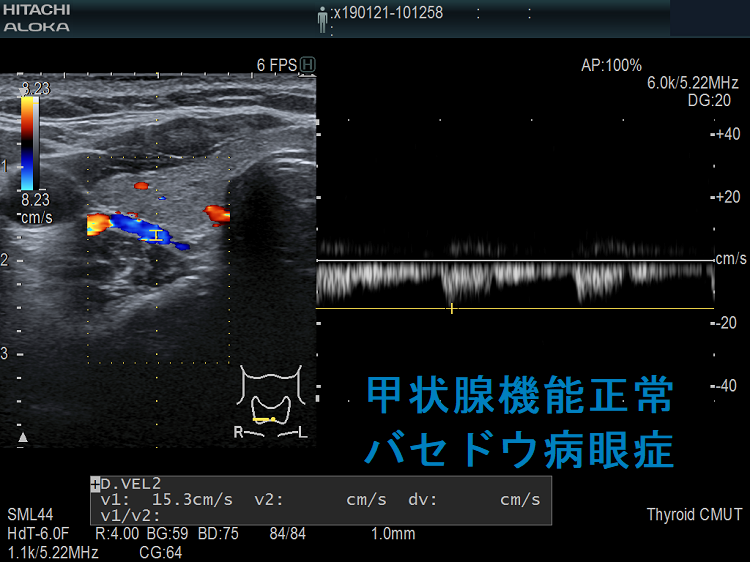

甲状腺ホルモンが正常なのに進行するバセドウ病眼症があります(甲状腺機能正常バセドウ病眼症)。

甲状腺機能正常バセドウ病眼症は、

- 片眼性が多いとされるが、両眼性のことも

- 活動性は低いとされるが、高活動性のことも

- TSAb 弱陽性。TSAbが正常上限値(110%未満が正常なので、100-109%)の事は多いが、強陽性のことも(下記)

- TRAb(通常のバセドウ病抗体)は陰性が多い(下記)

- 甲状腺腫は認めない事が多い

しかし、甲状腺機能正常バセドウ病眼症の40%は、甲状腺に99mTc(テクネシウム)シンチグラフィーの取り込み(集積)があり、甲状腺ホルモンが正常なのにバセドウ病は活動しています

99mTc(テクネシウム)シンチグラフィーの取り込み(集積)がある場合の甲状腺機能正常バセドウ病眼症は軽度でない

[Br J Ophthalmol. 1997 Dec;81(12):1080-3.]